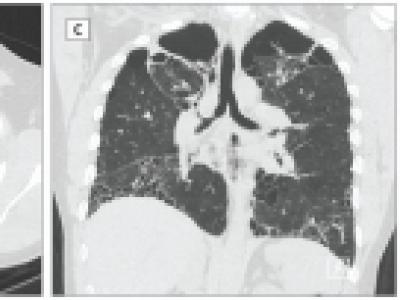

Good review of Diagnosis and Treatment of Pulmonary Sarcoidosis in JAMA. - Lung progression (in only 10%) assoc w/ 12-18% 5yr mortality - Sx Sarcoid w/ Lung: start Pred 20 to 40 mg/d for 2 -6 wks - Steroid sparing w/ MTX, AZA or TNFi https://t.co/aVnUXaj0sj https://t.co/JN142hlR6g